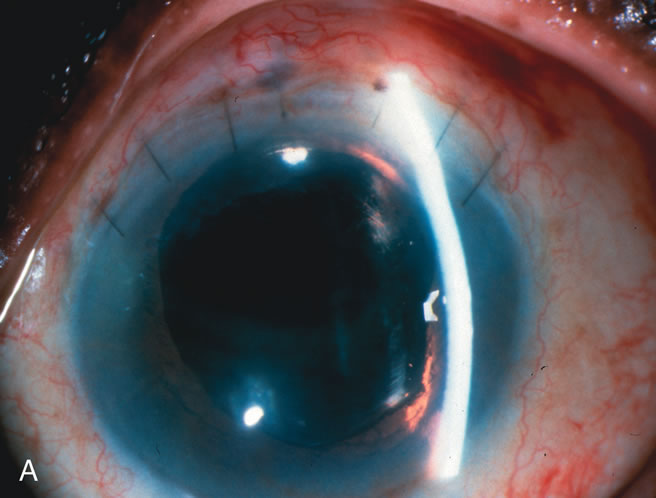

Fig. 5. Anterior chamber angle changes associated with lens extraction and PCIOL This 65-year-old Vietnamese woman has a long-standing history of chronic angle-closure glaucoma treated with laser peripheral iridectomy. The optic nerve demonstrated mild glaucomatous damage and IOP was moderately controlled on two antiglaucoma medications. The cataract was removed through temporal clear corneal phacoemulsification with foldable acrylic IOL. A. Symptomatic cataract in narrow-angle glaucoma eye with patent iridectomy. B. Intraoperative goniophotograph showing crowding of angle with increasing narrowness due to phacomorphic component. C. Intraoperative photograph showing temporal clear corneal approach with IOL in the capsular bag. D. Intraoperative goniophotograph demonstrating deepening of chamber angle following lens extraction. Proposed theories for IOP reduction following lens extraction with complete wound closure: